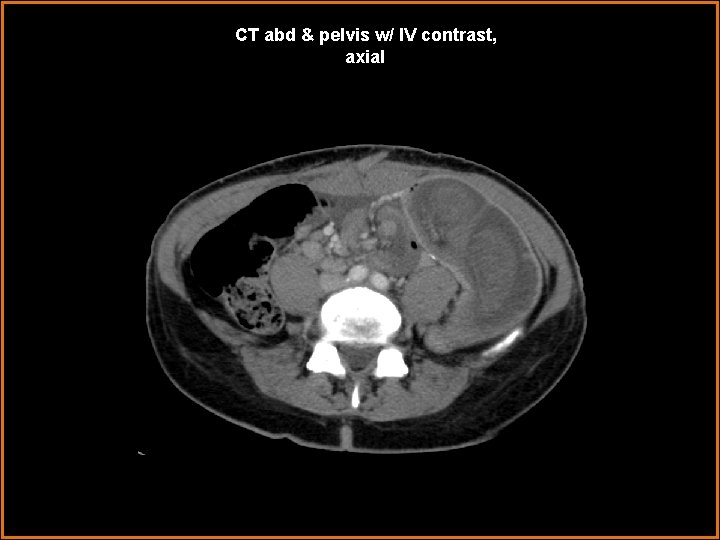

Case History 42 year-old female status-post gastric bypass operation within the last year presents with acute abdominal pain, nausea, and vomiting, for two days.

CT abd & pelvis w/ IV contrast, axial

Findings and Differentials Findings: -- several centimeters of small bowel lumen-within-lumen appearance—“target / bull’s eye” appearance, in axial cross-section -- mesenteric fat and vessels enter at the most proximal end of this small intestinal “telescoping” -- dilated immediate distal or outer aspect of the telescoping bowel-in-bowel segment -- however, decompressed distal small bowel and decompressing colon -- surgical anastomotic small intestinal clips in mid abdomen nearby segment of jejunum enters a segment of distal jejunum, near a post-operative site Differentials: • Intussusception • Midgut volvulus

Diagnosis Jejuno-jejunal intussusception, with partial small bowel obstruction converting to completion